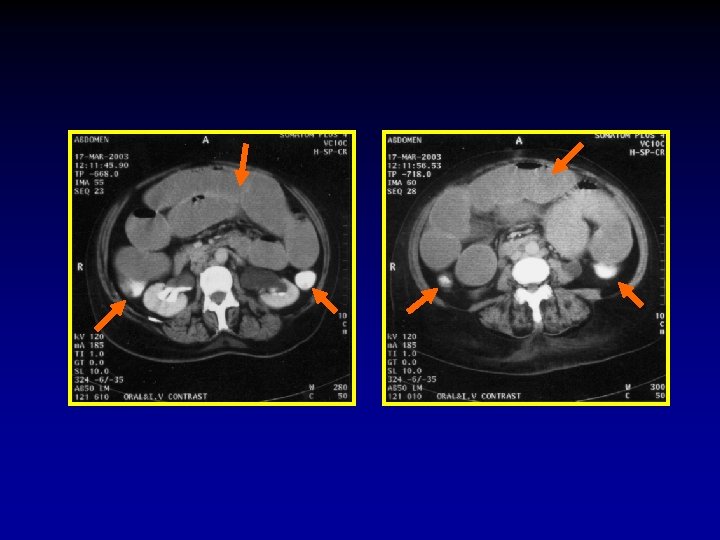

The CT signs of closed loop obstruction of the small intestine are: 1. Evidence of small bowel obstruction. 2. A U-Shaped or radial configuration of the fluid filled dilated loops. 3. At the site of obstruction, a whirl sign, beak sign, triangular loop, or two adjacent collapsed loops.

A At U-Shaped the site Evidence of configuration obstruction of. The small Whirl of two bowel theadjacent sign fluid obstruction. filled collapsed dilatedloops